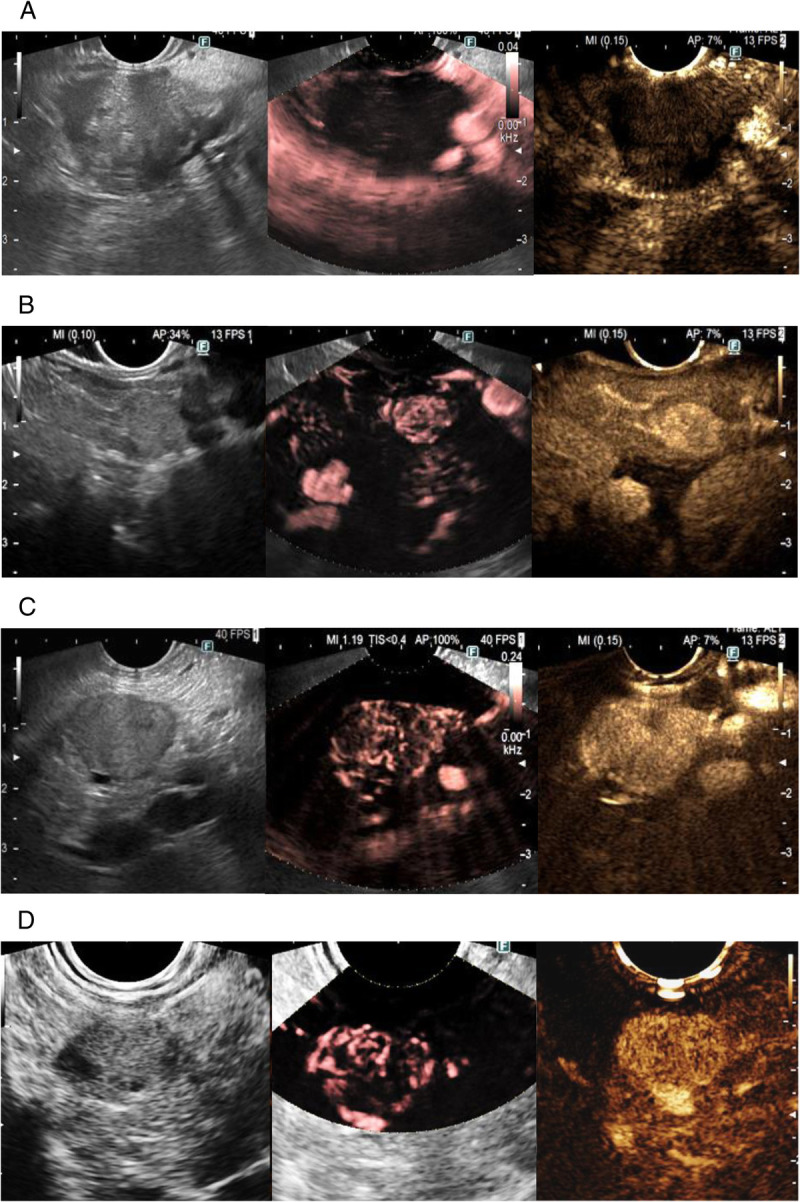

Background and objectives: Detective flow imaging EUS (DFI-EUS) is a new technology that detects fine vessels and low-flow velocity without contrast agents, used in real time during EUS, with a better resolution compared to usual technologies such as color Doppler and eFLOW. The aim of this study was to compare DFI-EUS with contrast-enhanced EUS (CE-EUS) for the evaluation of vascularization in solid pancreatic lesions.

Methods: We included patients who had a pancreatic mass visualized by EUS, with recorded images of their assessment in DFI-EUS and CE-EUS techniques and a histological diagnosis confirmed malignant tumors or a minimum of 1-year follow-up for benign lesions.

Results: Of the 107 patients included in this retrospective single-center study, the histological diagnosis revealed 69 cases (64.5%) of pancreatic adenocarcinoma, 18 cases (16.8%) of neuroendocrine tumors (NETs), and 10 cases (9.3%) of metastases from nonpancreatic cancers. A smaller proportion (9.4%) exhibited other lesions. As a result, the incidence of intralesional microvascularization was 43.9% with DFI-EUS and 48.6% with CE-EUS, indicating a positive correlation between the 2 techniques (P = 0.0001). Compared to CE-EUS, DFI-EUS exhibited sensitivity, specificity, positive predictive value (PPV), and negative predictive value (NPV) of 88.5%, 98.2%, 97.9%, and 90%, respectively, for the detection of intralesional vessels.

Conclusions: The novel technique DFI-EUS demonstrates a remarkable correlation with CE-EUS, exhibiting high sensitivity and specificity for the assessment of microvascularization in solid pancreatic lesions. This method eliminates the need for a contrast agent, thus carrying no risk of adverse effects.